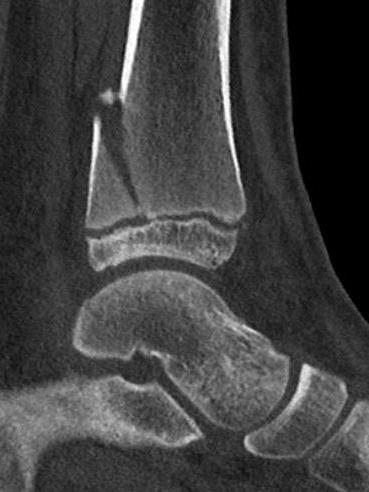

Triplanar Fracture

Definition

Fracture in coronal, sagittal and transverse planes

- crosses epiphysis

- passes through growth plate

- extends into metaphysis

Xray

AP xray: Salter-Harris type III / Tillaux

Lateral xray: Salter-Harris Type II

CT

Coronal images: Salter-Harris type III

Sagittal images: Salter-Harris type II

Axial images: 3 point star